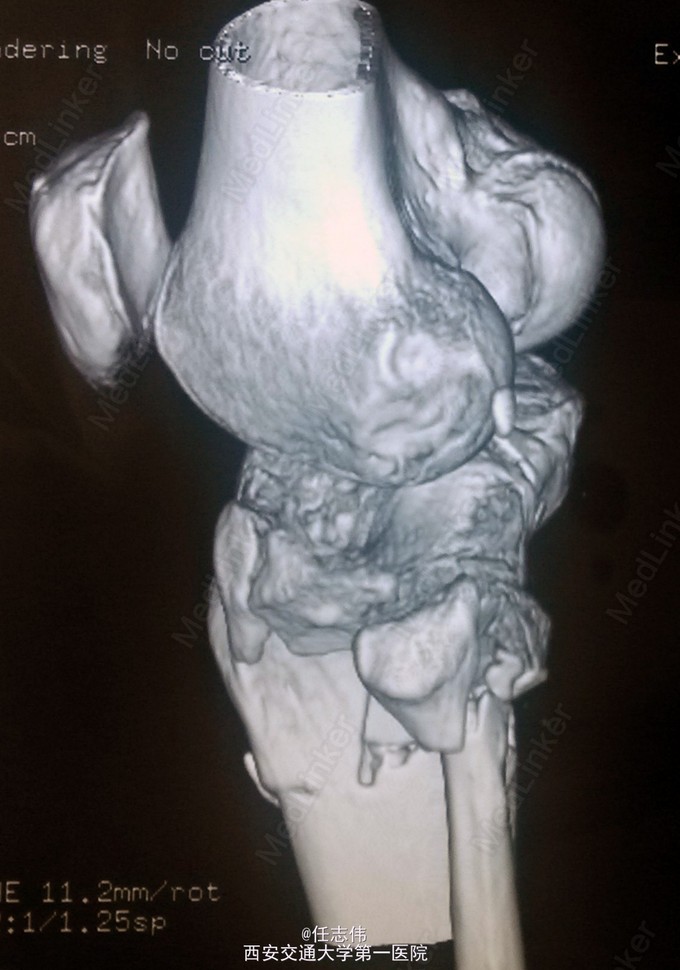

女性,66岁,摔伤致左膝部疼痛活动受限7天 7天前摔伤致左膝部疼痛伴活动受限,在当地医院行跟骨牵引、消肿对症治疗7天,已基本消肿,足部感觉、活动、血供正常。 既往有糖尿病史。

左膝关节周围肿胀,胫骨平台处压痛明显,外侧为著,膝关节活动受限。左足背动脉搏动好,踝及足趾感觉活动正常。

诊断:右胫骨平台骨折 处理:骨折切开复位内固定术。行内外侧入路钢板固定,术中行外侧平台塌陷复位,髂骨植骨内固定。另因考虑有后柱骨折,遂行后外侧切口,支撑钢板固定。术中见患者骨质疏松明显。 术后伤口愈合好,局部仍肿胀明显。

有几个问题想问问: 1.这个是胫骨平台骨折吗?还是胫骨近端骨折伴有平台骨折。 2.手术处理上有什么建议?可以不处理后侧柱吗? 3.大家在复位塌陷平台上有和经验?